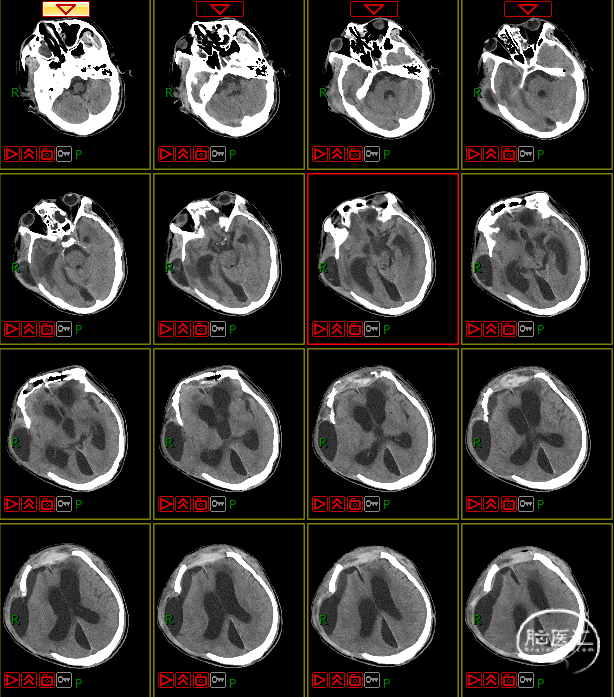

病史及症状描述:主诉:重型颅脑外伤术后意识障碍50天(7月30日入院);现病史:患者2023年6月11日因高处坠落伤在外地行开颅手术等治疗,病情平稳后带气管套管转回湘潭市中心医院(后续简称“我院”)治疗。

入院查体:GCS=E2VTM2=4T分,右侧瞳孔直径约4mm,对光反射迟钝,左侧瞳孔约3mm,对光放射灵敏,四肢关节被动屈伸活动无受限,四肢肌张力偏高,肌力查体无法配合,病理征未引出。

入院诊断:1. 右侧额颞部硬膜下血肿清除术后;2. 颅骨后天性缺损;3. 脑内多发软化灶形成;4. 脑积水;5. 左额骨凹陷性骨折;6. 颅底骨折;7. 左股骨干骨折内固定术后;8. 坠积性肺炎、胸腔积液;9. 气管切开术后;10. 右眼挫伤;11. 下肢肌间静脉血栓;12. 低蛋白血症。

4. 动态复查头部CT

8月21日复查CT:硬膜下积液增加,脑室扩张明显,间质性水肿加重;对患者治疗方案进行调整,转神经外科治疗。